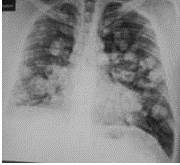

En vista de los hallazgos y la persistencia de cuadro clínico, se practica radiografía de tórax observándose en la proyección póstero-anterior (PA) múltiples nódulos pulmonares bilaterales a nivel central y sub-pleural, con broncograma aéreo, con áreas de opacidad en vidrio esmerilado (Figura1). Para completar el estudio se decide realizar una tomografía computarizada de tórax con tomógrafo BRIGHT SPEED ®de 16 detectores sin la administración de contraste intravenoso. En la ventana pulmonar se evidencia múltiples imágenes nodulares a nivel central y sub-pleural bilateral con tamaños que oscilan entre 0,6 cm y 3,1 cm, con valores de atenuación entre 23-43 UH. Se aprecia un aumento en la atenuación pulmonar con broncograma aéreo, asimismo, opacidades en vidrio esmerilado periférico bilateral, engrosamiento septos inter-lobulillares a predominio basal (Figura 2). No se observan ganglios hiliares o mediastínicos aumentados de tamaño para ser considerados patológicos desde el punto de vista tomográfico, asimismo, no se observó derrame pleural.